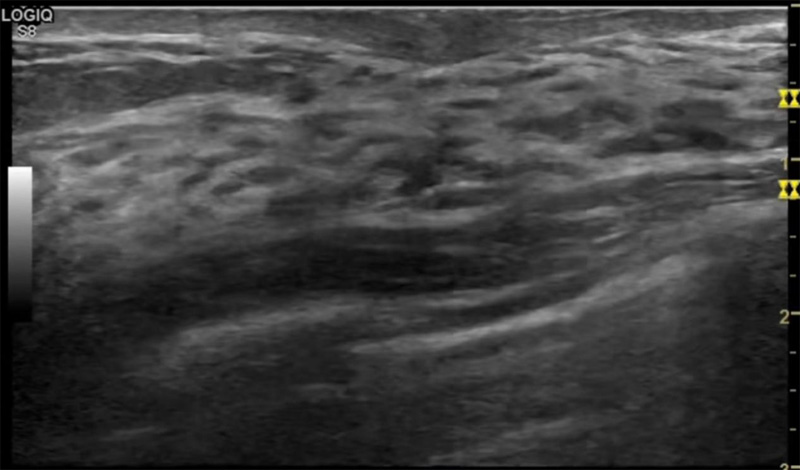

乳房胀痛,触摸疼痛,手摸起来感觉有肿块。这个是什么问题呢?医生诊断一般是乳腺增生。那么在乳腺超声设备检查后,报告单却显示双乳未见明显占位性病变。乳腺增生是很多女性,特别是育龄期女性都有的经历、到底乳腺增生症状有哪些?会给我们带来怎样的影响呢?乳腺增生不是肿瘤跟炎症。乳腺组织增生及退行性变跟内分泌功能紊乱有关系。正常的生理改变。还有乳腺病,良性乳腺结构不良等名称。

乳腺增生有什么症状,病因?比较典型的就是乳房疼痛,特别是经前症状比较重,经后就有所缓解。有时候还能碰到乳房硬块。根据经期的变化而变化硬度大小都有变。乳腺在内分泌激素,伴随月经周期有增生问题。内分泌激素代谢失衡,雌激素水平增高,出现乳腺组织增生过度,增生组织不退的情况下,就会有乳腺增生症状。这个不会增加乳腺癌的风险。所以不用紧张的。不过乳腺癌的病人都会有乳腺增生。所以乳腺增长有没症状,都需要进行常规的体检。